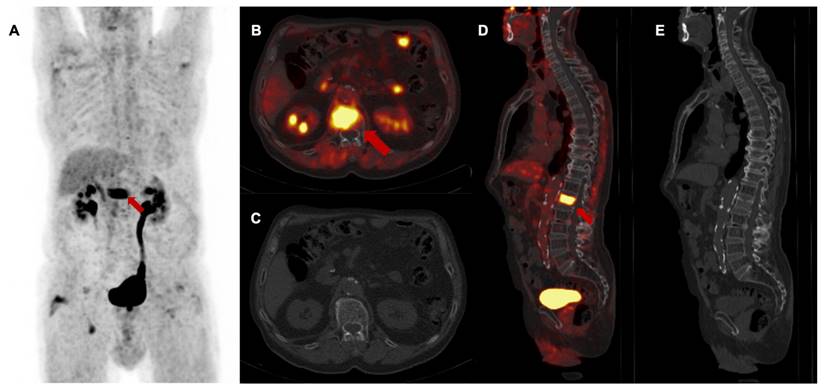

Figure 5

3rd follow-up [68Ga]Ga-FAPI-46 PET/CT of a patient with locally recurrent pancreatic adenocarcinoma 9 months after chemoradiotherapy (Patient #2) A maximum intensity projection, B and D transaxial and sagittal PET/CT fusion, C and E contrast-enhanced CT scan (bone window). Red arrows (A, B, D) mark intense FAPI signal of first lumbar vertebra without a detectable lesion in the bone. In the absence of any morphological finding in the CT scan, this scan was classified as M upstaging and, in the consensus of an interdisciplinary tumor board, considered as singular metastatic spread to the bone. Biopsy and histopathological confirmation were not performed. The patient received curative intended local radiotherapy of the first lumbar vertebra.

M staging at follow-up

Follow-up [68Ga]Ga-FAPI-46 PET/CT showed a high rate of M upstaging, including a change of classification from M0 to M1 or the detection of different metastatic lesions compared to CT alone in seven of 13 patients (53%) at first follow-up, in two of seven patients (29%) at second follow-up and in three of four patients (75%) at third follow-up. Intense FAPI uptake without a measurable lesion in the CT scan was suspicious for metastatic spread at the following sites: 44% peritoneum, 25% liver, 13% soft tissue, 8% bone, brain and lung. In total, additional diagnostic measures were taken in five of 24 scans (21%) (5/24), including mainly liver and brain MRIs. In one patient with LRPAC, who maintained local tumor control up to the third follow-up scan, diffuse FAPI signaling of a lumbar vertebra with unremarkable bone structure occurred and was staged as oligometastatic spread to the bone, which was followed by ablative radiotherapy (Figure 5). After radioablation, the follow-up scans showed a significant decrease in FAPI uptake, indicating treatment response of the initial osseus tumor burden.